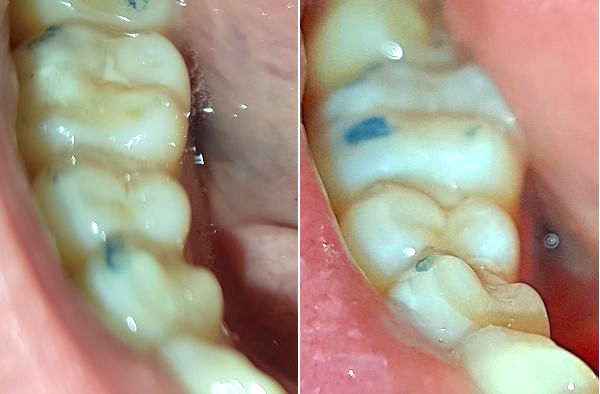

24-jähriger Patient (17.11.2025 / 8888)

Anamnese: Der Patient musste wegen einer kieferorthopädischen Behandlung 4+4 ziehen und 765+567 nach vorne verschieben lassen. Deshalb ist eine Minderbelastung des Kauzentrums 6-6 entstanden. Um besser kauen zu können, hat er nur noch links gebissen. Dabei ist aber +7 elongiert und ein Vorkontakt auf +-7 entstanden, der ihn störte. Er hat deshalb schon fünf verschiedene Knirscherschienen erhalten.

Therapie: Die mesialen Höcker des Zahnes 6- konnten ganz einfach mit Komposit erhöht werden.

Das Kaugefühl war dann sofort besser.

In der nächsten Sitzung wird auch noch der Zahn 5- erhöht, um das Kauzentrum noch etwas mehr zu vergrössern.

Vorbehalt: das Kaugefühl ist gut geblieben.

24-jähriger Patient (29.01.2026 / 8888)

Der Patient hatte nach der kieferorthopädischen Behandlung kein gutes Bissgefühl. Die Anfärbung zeigt, dass die wichtigsten Molaren 6-6 fast nicht belastet werden.

Mit Komposit wurde auf die Molaren 76-6 je ein Witzgall-Höcker aufgesetzt. Diese befinden sich nicht am gewöhnlichen Ort, sondern dort, wo sie den Biss am besten unterstützen. Bei der kieferorthopädischen Behandlung mussten die oberen Molaren etwas nach vorne verschoben werden und passten deshalb nicht mehr gut zu den unteren.